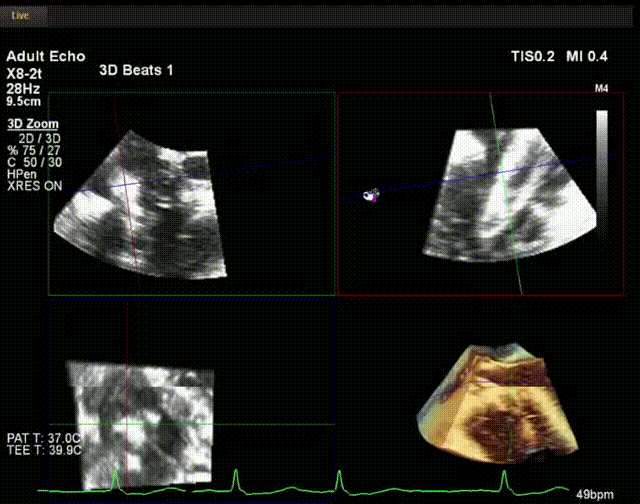

術(shù)中超聲